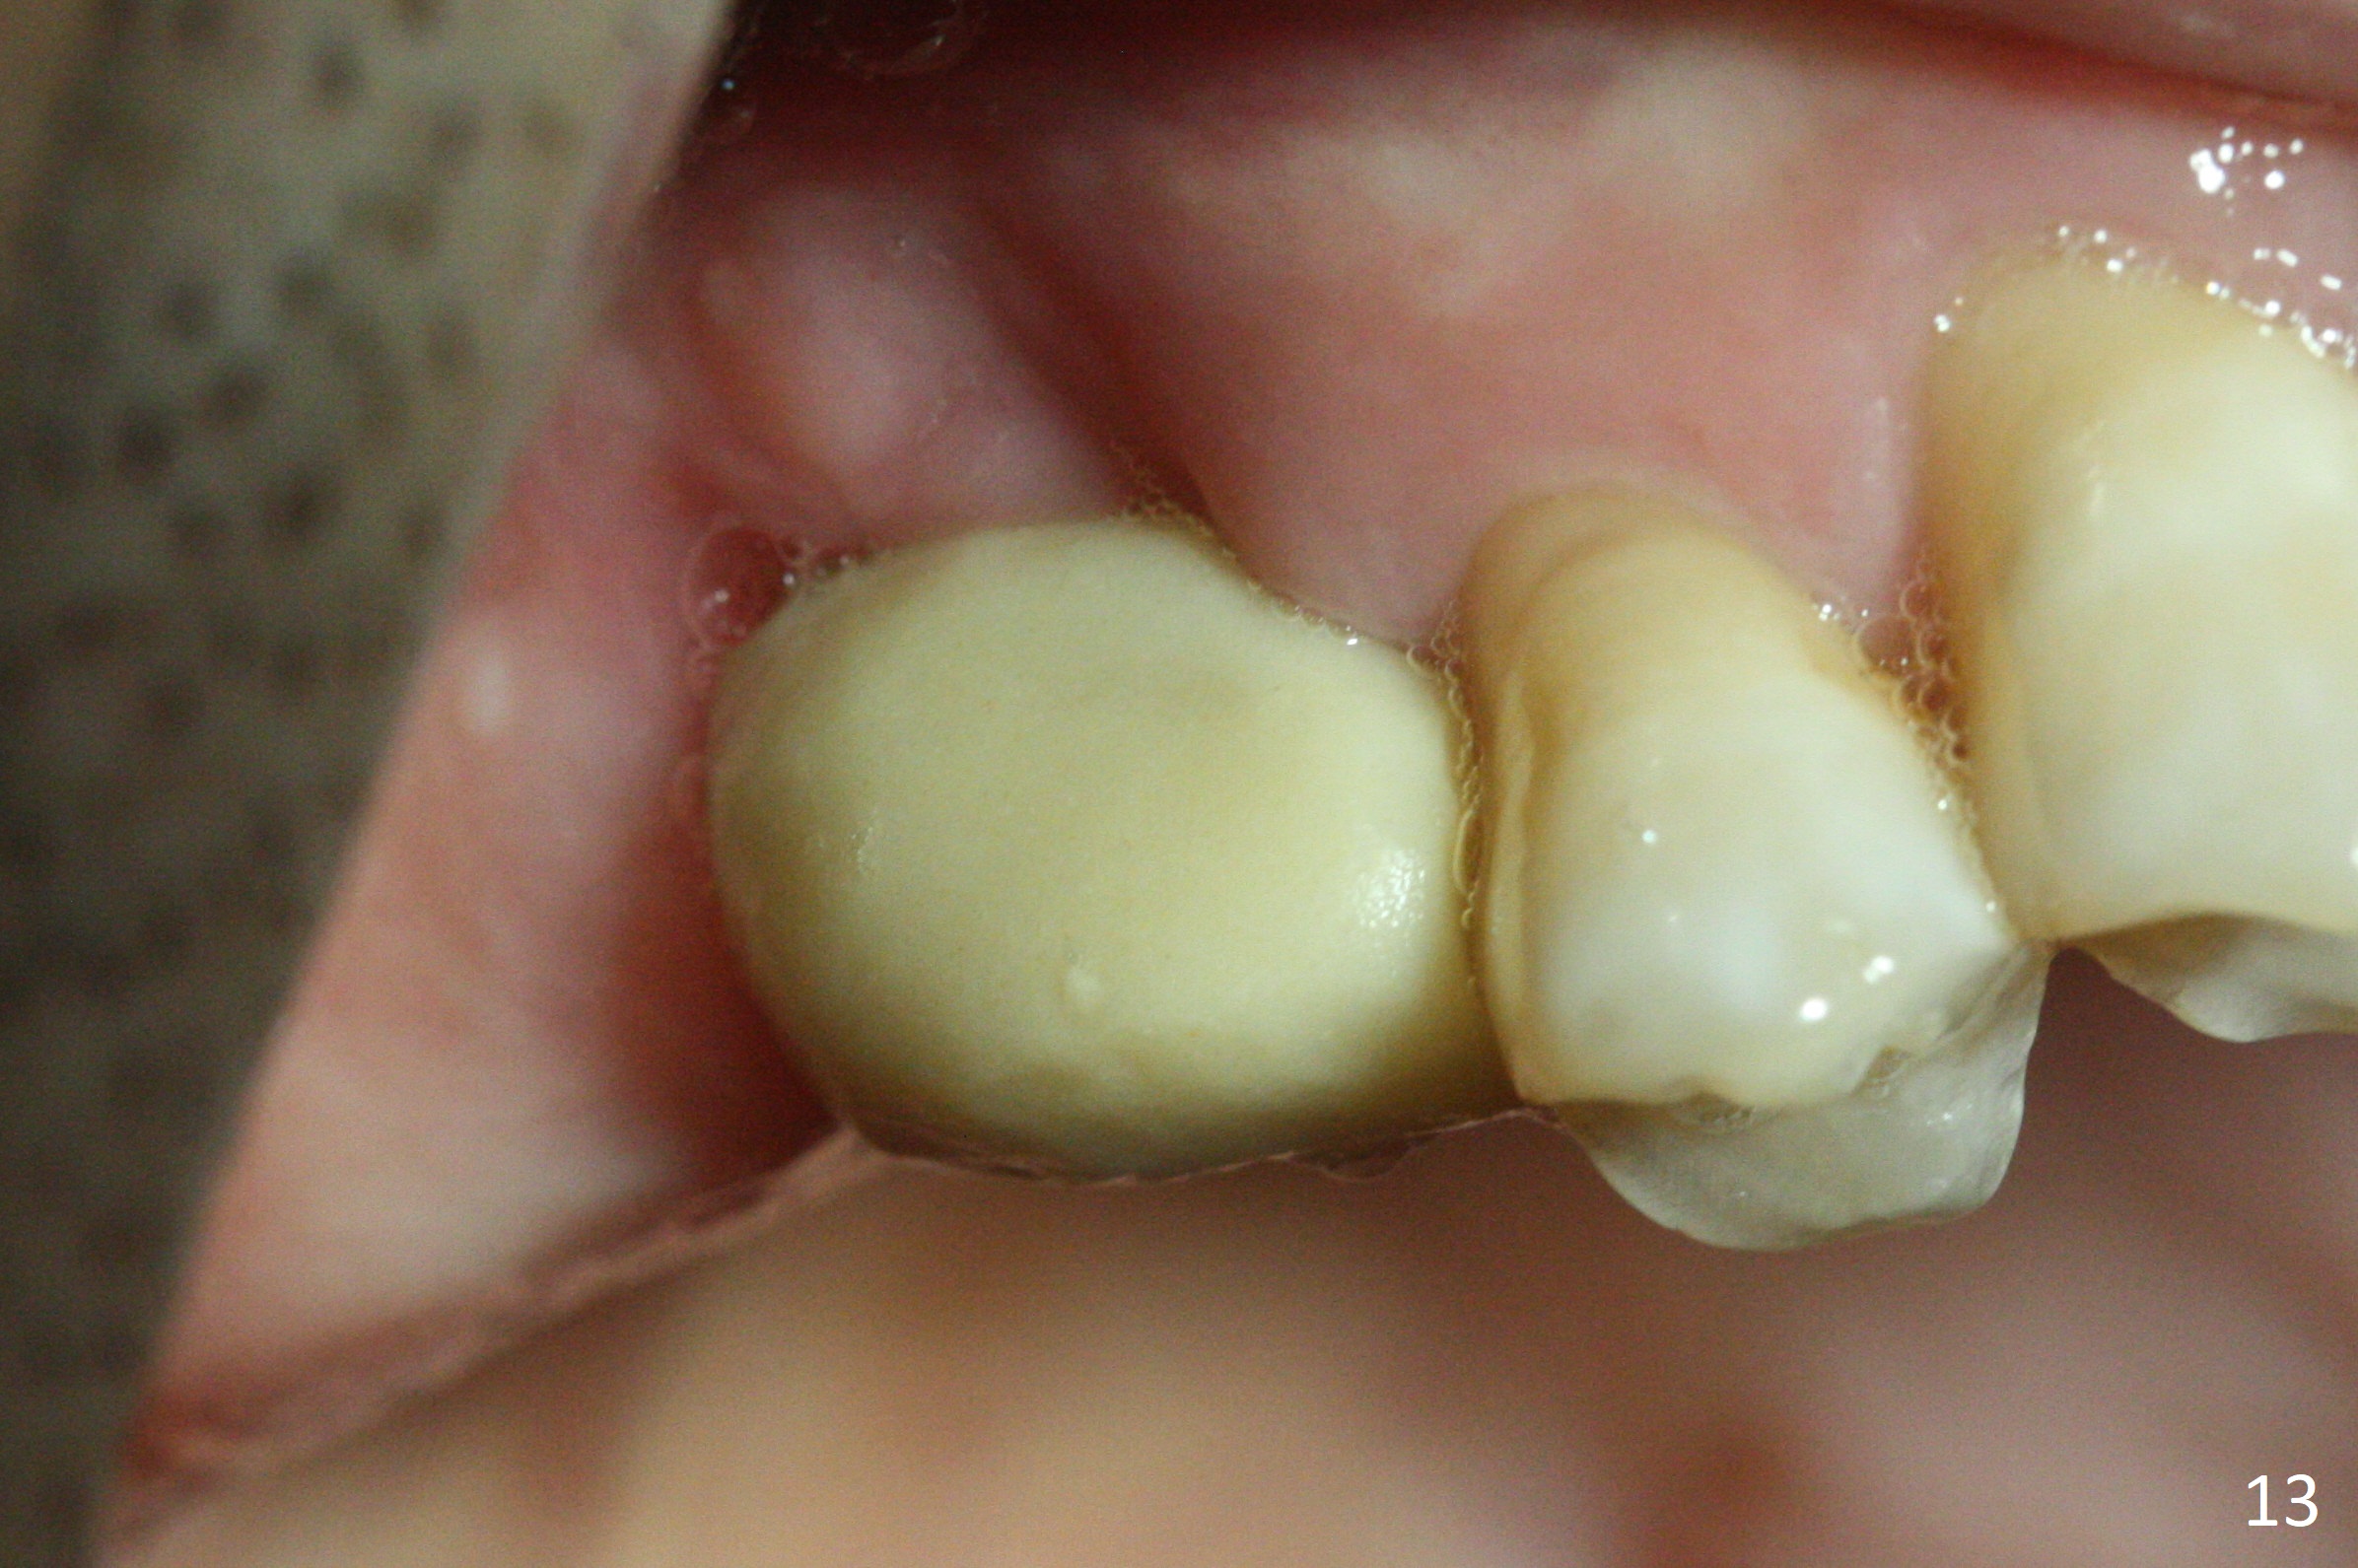

Two weeks later, the buccal gingiva appears to have grown downward (Fig.13). Fig.14 is taken when the provisional is removed. To facilitate this process, change abutment from 4.8x7(3) to (4.5) mm and a new provisional is fabricated (Fig.15): note the metal exposure distobuccally. When the patient returns in another two week, the gap should be able to disappear. There is no loss of bone graft 3 months postop (Fig.16). Two weeks later (3.5 months postop), the margin of the abutment is supragingival buccally and subgingival palatally (Fig.17,18). The gingiva seems to have migrated downward (Fig.19 arrow), while the bone density around the coronal implant appears to increase 5.5 months post cementation (Fig.20). There is buccal swelling with purulent discharge 1.5 years post cementation (Fig.21). Perimplantitis develops. Tuberosis bone graft will be performed when the limited ortho is finished.